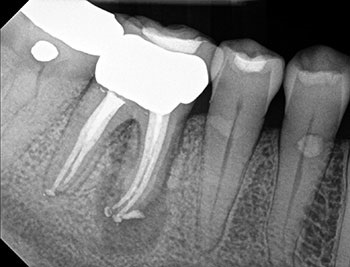

Case 2: A U-shaped lesion

Tooth #30 presented with a diagnosis of previously treated and symptomatic apical periodontitis. The radiographic lesion encompassed both sides of the mesial root, forming a U-shaped lesion. Periodontal probing extended to the apex. The prior endodontic root preparations were relatively large, compared with the root canals on the patient’s other untreated teeth. Because the bone loss associated with a U-shaped lesion encompasses both sides of a root, it might be considered even more indicative of a potential VRF than a J-shaped lesion.

This patient had been examined by an endodontist, who recommended extraction because of a VRF. Although multiple risk factors were identified, no fracture was seen upon access, and this tooth was successfully retained through nonsurgical retreatment.

Fig. 5: Preop PA.

Fig. 7: Recall PA.